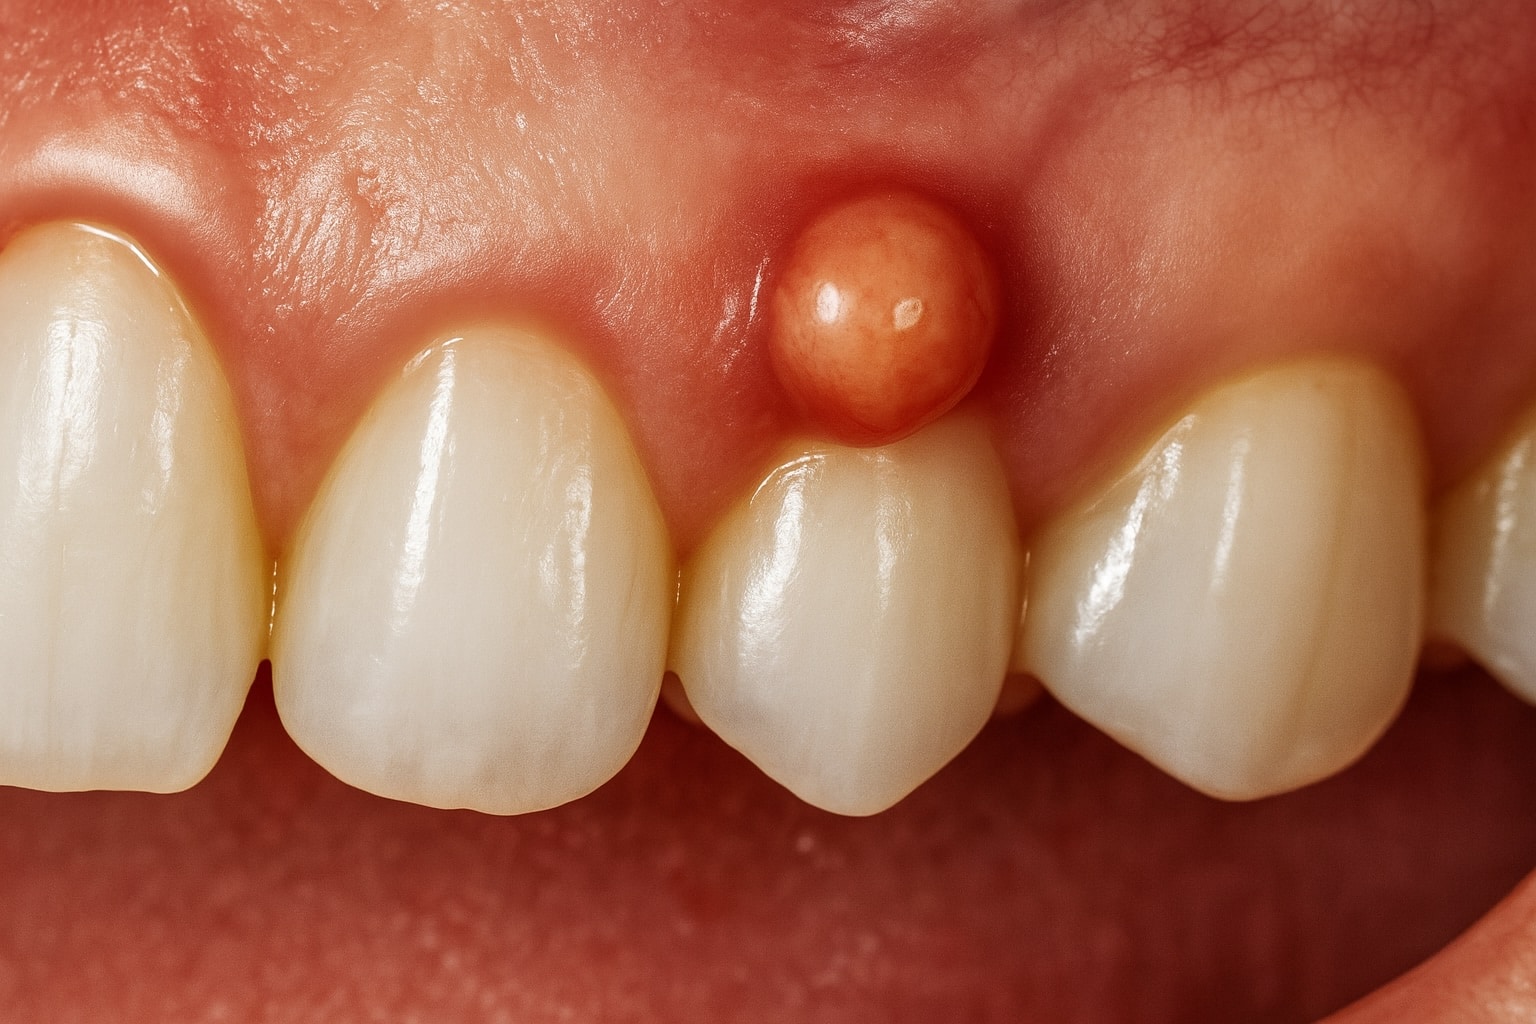

Un absceso dental es una acumulación de pus causada por una infección bacteriana que se localiza en la zona de un diente o en los tejidos que lo rodean. Esta infección puede aparecer por diversas causas y se manifiesta generalmente con dolor, inflamación, mal aliento y, en algunos casos, fiebre.

- Mal sabor de boca o pus visible

Absceso periapical

Se produce cuando la infección se origina en la pulpa del diente y se extiende hasta el extremo de la raíz. Es común en dientes con caries profundas o traumatismos sin tratar.

Drenaje de un absceso dental

En ciertos casos, será necesario realizar un drenaje profesional para eliminar el pus acumulado. Este procedimiento se realiza en consulta y puede ir acompañado de un tratamiento complementario como la endodoncia o la limpieza profunda, según la gravedad del caso.